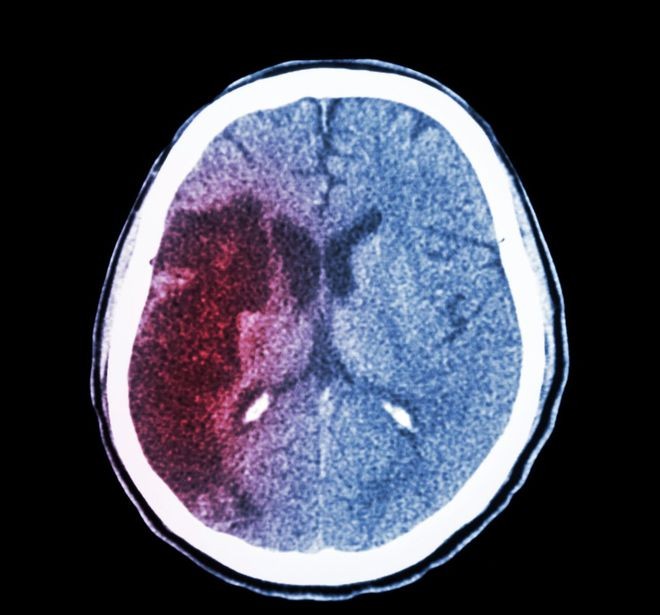

Xuất huyết não “giết người nhanh nhất”, 4 dấu hiệu trước khi khởi phát nhưng dễ bị bỏ qua

Căn bệnh này được mệnh danh là "kẻ giết người nhanh nhất" và được biết đến với sự khởi phát nhanh chóng, là căn bệnh số một gây ra cái chết của người trung niên và người cao tuổi ở Trung Quốc.

Nguyên nhân xuất huyết não

Nếu huyết áp tăng vượt quá khả năng co bóp tối đa của cơ trơn tiểu động mạch não, mạch máu sẽ giãn ra một cách thụ động, cơ trơn bị tổn thương, tính thấm tăng, sự xâm nhập của các thành phần huyết tương sẽ dẫn đến hoại tử sợi tiểu động mạch, cơ trơn tiểu động mạch trở nên trong suốt. Thành mỏng và phồng lên thành những túi phình nhỏ; thành tiểu động mạch và những túi phình nhỏ bị vỡ khi huyết áp tăng đột ngột là nguyên nhân phổ biến nhất gây xuất huyết não.

Di chứng xuất huyết não

Đối với bệnh nhân xuất huyết não, nhu mô não sau khi xuất huyết sẽ bị tổn thương ở một mức độ nhất định, tương ứng sẽ có những trở ngại về chức năng của não, do đó, dù điều trị nhưng những bệnh nhân vẫn để lại những di chứng ở mức độ khác nhau. Triệu chứng phổ biến nhất của di chứng xuất huyết não là liệt nửa người, biểu hiện là giảm sức cơ của một chi, cử động không thuận lợi hoặc hoàn toàn, thường kèm theo rối loạn cảm giác của chi như mất cảm giác. Đôi khi, nó cũng có thể đi kèm với các khuyết tật trường thị giác hai bên.